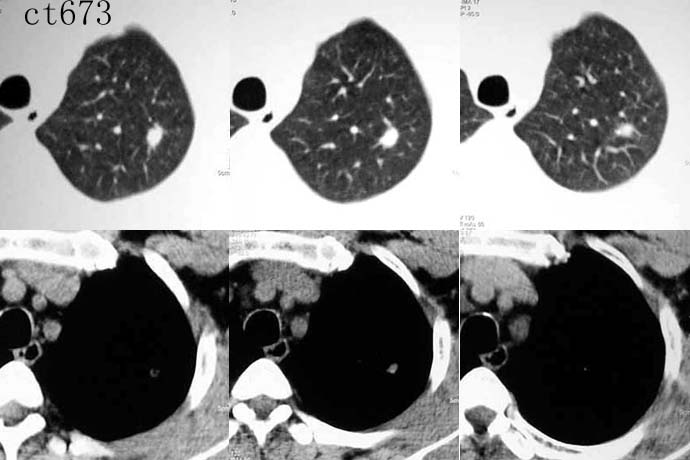

ct2533:张巍 提供 患男,24岁,胸痛数月.

穿刺活检为干酪坏死物.胸壁结核瘤!

ct1240:song7715

病人24岁,身体偏瘦,半月前曾有高烧,现无阳性体征,血项不高。透视时无意发现。

右肺结节病理结果:结核球http://www.radida.com/radinet/read.php?tid=3611

ct1585:liuwensi 提供

m,64y,体检发现右肺上叶后段孤立性结节,纵隔内未见肿大淋巴结影右肺病理是结核球

http://www.radida.com/radinet/read.php?tid=4599